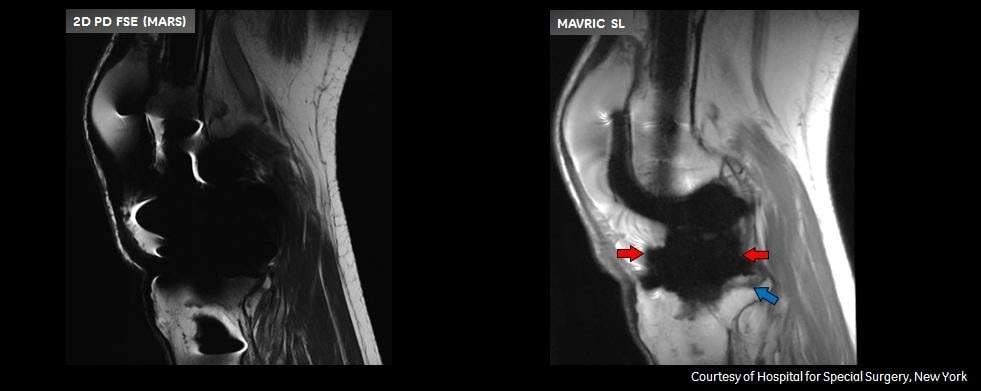

Patients with complications from joint replacement surgeries may present with pain and/or altered gait mechanics, or may have no symptoms at all. Prior to the availability of Mavric SL, achieving quality diagnostic MR images of the anatomy near implants was often not possible due to image distortion caused by metal used in implanted devices. Mavric SL reduces image distortion in the regions near MR conditional metal implants, enabling physicians to see tissue surrounding an implant to help them with diagnosis and defining a course of treatment. In some cases, Mavric SL can reduce the need for biopsy or exploratory surgery.

Mavric SL is a combination of an acquisition technique and post-processing software intended for use on GE 1.5T and 3.0T MR systems. Mavric SL is suitable for use on all patients with passive MR conditional orthopedic implants that are scanned according to the conditions of safe use for the specific MR conditional implant being scanned. In addition, Mavric SL is suitable for use on patients without implants that are cleared for MR exams. Mavric SL helps reduce artifacts caused by presence of metal in both in-plane and through-plane dimensions compared to conventional MR imaging techniques. Thus Mavric SL allows visualizing more tissue in the vicinity of MR conditional implanted metal instrumentation. When interpreted by a trained physician, images generated by Mavric SL provide information that can be useful in determining a diagnosis. Mavric SL is non-invasive, radiation-free and needle-free as it requires no contrast media injection. Mavric SL received Food and Drug Administration (FDA) 501(k) clearance in December 2012 and is available in most markets.